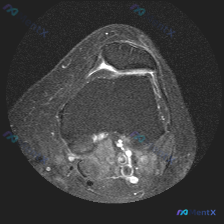

看到这份踝关节MRI读片资料,整理出来和大家分享分析思路。 病例基本影像信息 这是踝关节MRI轴位T2加权图像,先给大家梳理影像上的基本发现: 1. 骨骼结构:距骨、外踝(腓骨远端)、内踝(胫骨远端后部)骨皮质连续,无骨折或骨质破坏,骨髓信号均匀,无异常骨髓水肿 2. 肌腱与韧带:腓骨长/短肌腱、跟...